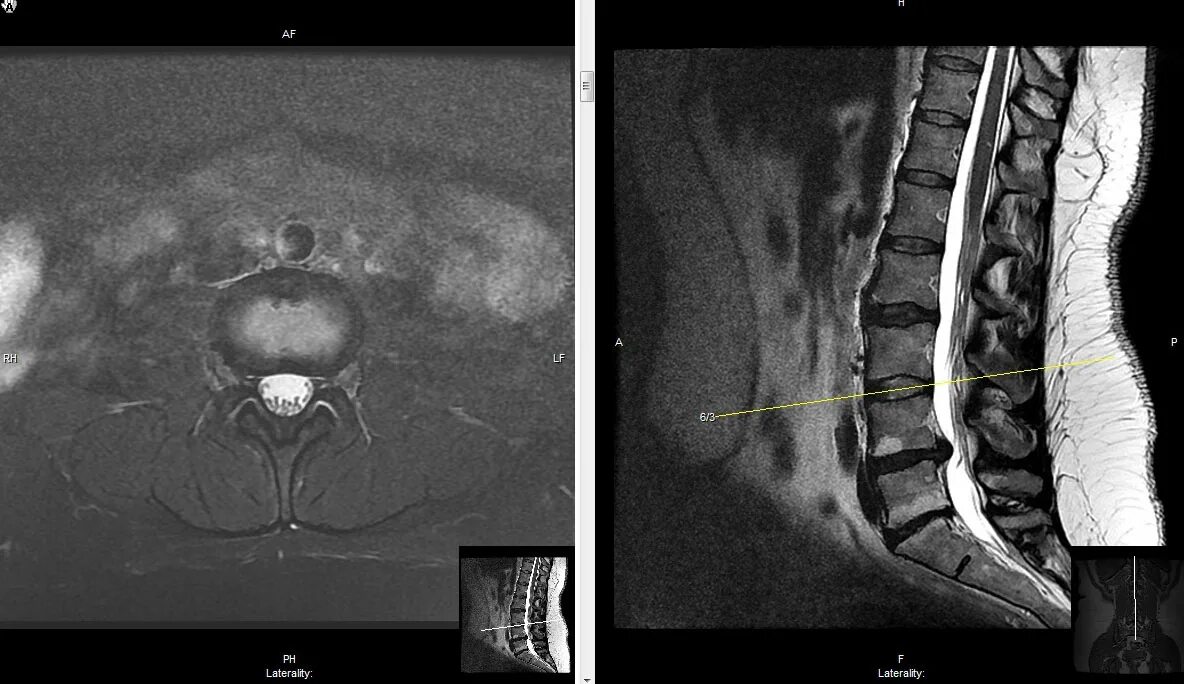

Протрузия дисков с5